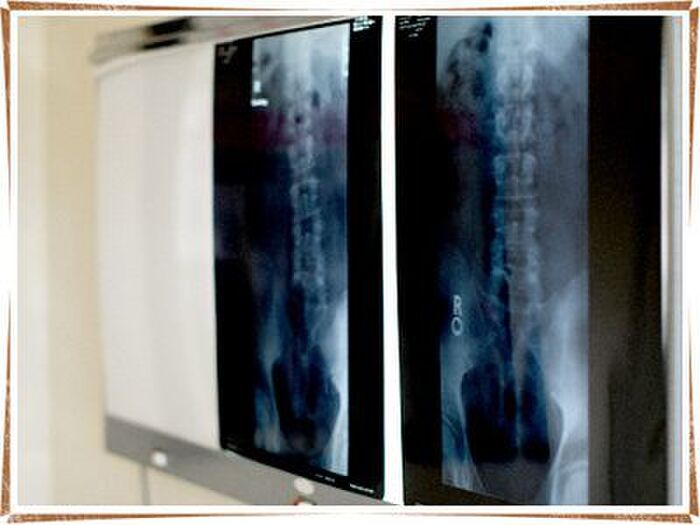

シリカ(ケイ素)が不足することで起きる骨粗しょう症とは、一体どのような病気なのでしょうか?

簡単にいってしまうと、骨の量自体が減少することで強度を失い、骨自体が弱くなってしまう症状がでてくるといわれています。

具体的な症状としては「立ち上がる時、重いものを持って体を起こすときに背中や腰が痛む」「背中を下にして眠りにくくなる」「骨折をしやすくなる」「身長が縮んでしまう」「背中や腰が曲がってしまう」など、日常生活に支障をきたしてしまうものばかりです。